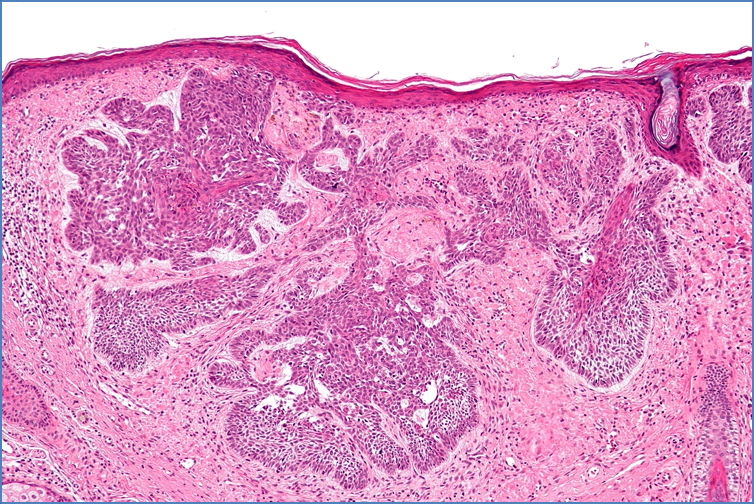

Microscopy

• Clusters of blue-staining basal cells

• Palisading nuclei (cells arranged peripherally like fence posts)

• Cells invade deeply into the dermis

• Pleomorphic basal cells with scant cytoplasm

• Mucinous stromal background often present